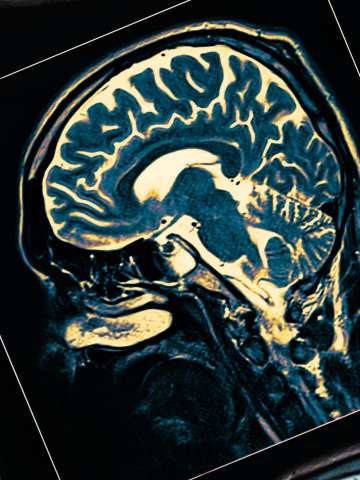

Cerebrovascular Neurosurgery

Our fellowship-trained cerebrovascular surgeons use the most sophisticated techniques to safely and effectively treat a variety of cerebrovascular conditions.

Receiving a diagnosis of cerebrovascular disease can be frightening, and chances are you have a lot of questions and concerns. UCLA Health understands this and we are here to help. If you have a vascular disorder of the brain – also called a cerebrovascular disorder – where you go for treatment is crucial. These conditions require surgeons who have the skill and expertise to manage them effectively. And that’s exactly what you can expect from the UCLA cerebrovascular team.

At UCLA Health, our team of experts provides each cerebrovascular neurosurgery patient with a comprehensive evaluation, imaging and other diagnostic testing. We then formulate a customized treatment plan. Conditions that we treat include: